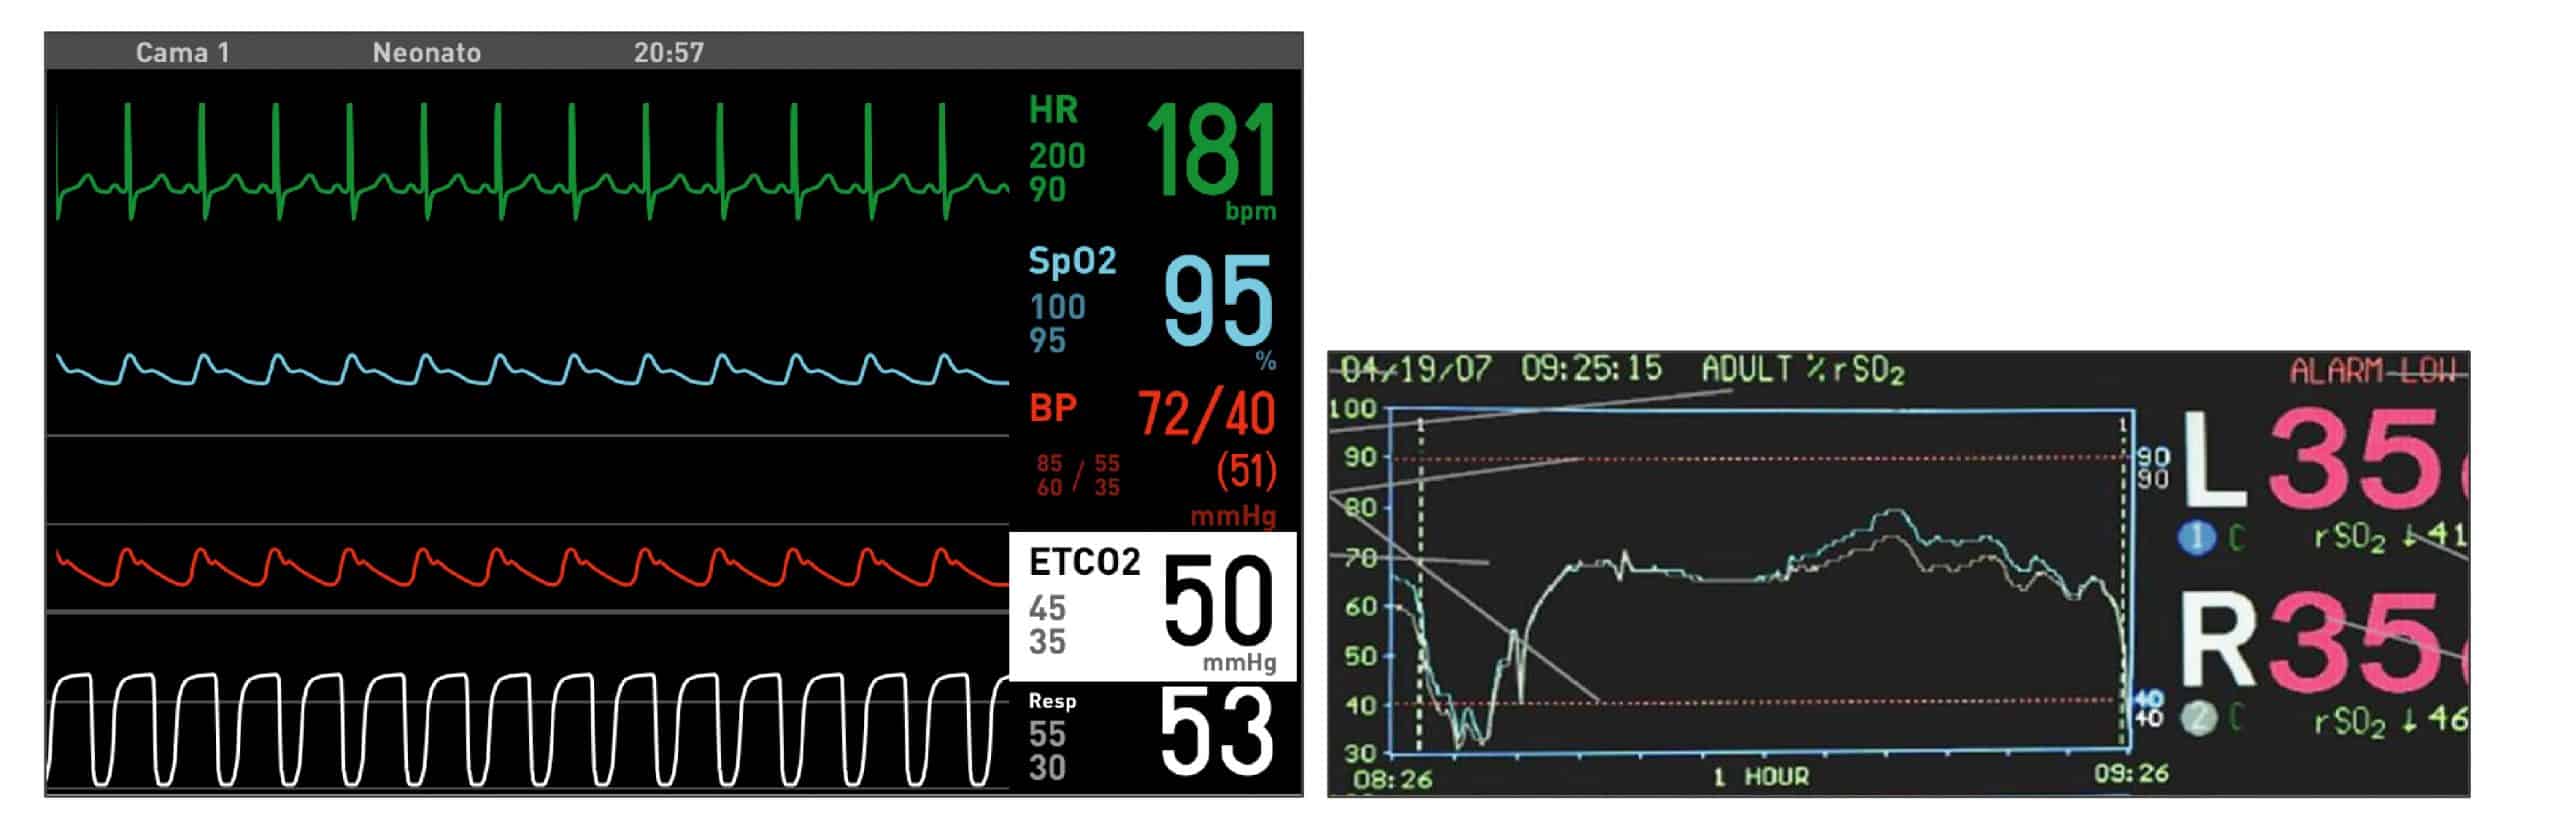

Se trata de un paciente, como se puede visualizar en la imagen, que en el momento de la extubación estaba taquicárdico, con unas tensiones medias adecuadas y polipneico.

En la pantalla del monitor se observó, como se puede ver en la imagen:

- Índice cardiaco (IC) de 2.1 /min/m2

- Volumen sistólico (SV) de 18 m/m2

- Resistencia vascular sistémica (SVR) de 1.700 dynas·seg3/cm3

- dP/dtmáx. de 0.9 mmHg/ml

- Ciclo de eficiencia cardiaca (CCE) de -0.18

- DO2 de 110 ml/min

Situación clínica de bajo gasto cardíaco

Los datos de MostCare Up apoyaban la baja vasoconstricción periférica con unas resistencias periféricas elevadas, irritabilidad continua, no solo por el edema, también por la situación de bajo gasto cardiaco con hipertensión y taquicardia, y una situación, por la congestión pulmonar, de polipnea con tiraje moderado.

- Acidosis metabólica.

- Elevación de láctico.

- Descenso SvO2 e INVOS, con aumento del IEO desde la extubación.

- Edema agudo de pulmón.

- E/E’ > 20, relación E/A >2.

- Patrón restrictivo.

- Volumen aurícula izquierda elevado desde la cirugía.